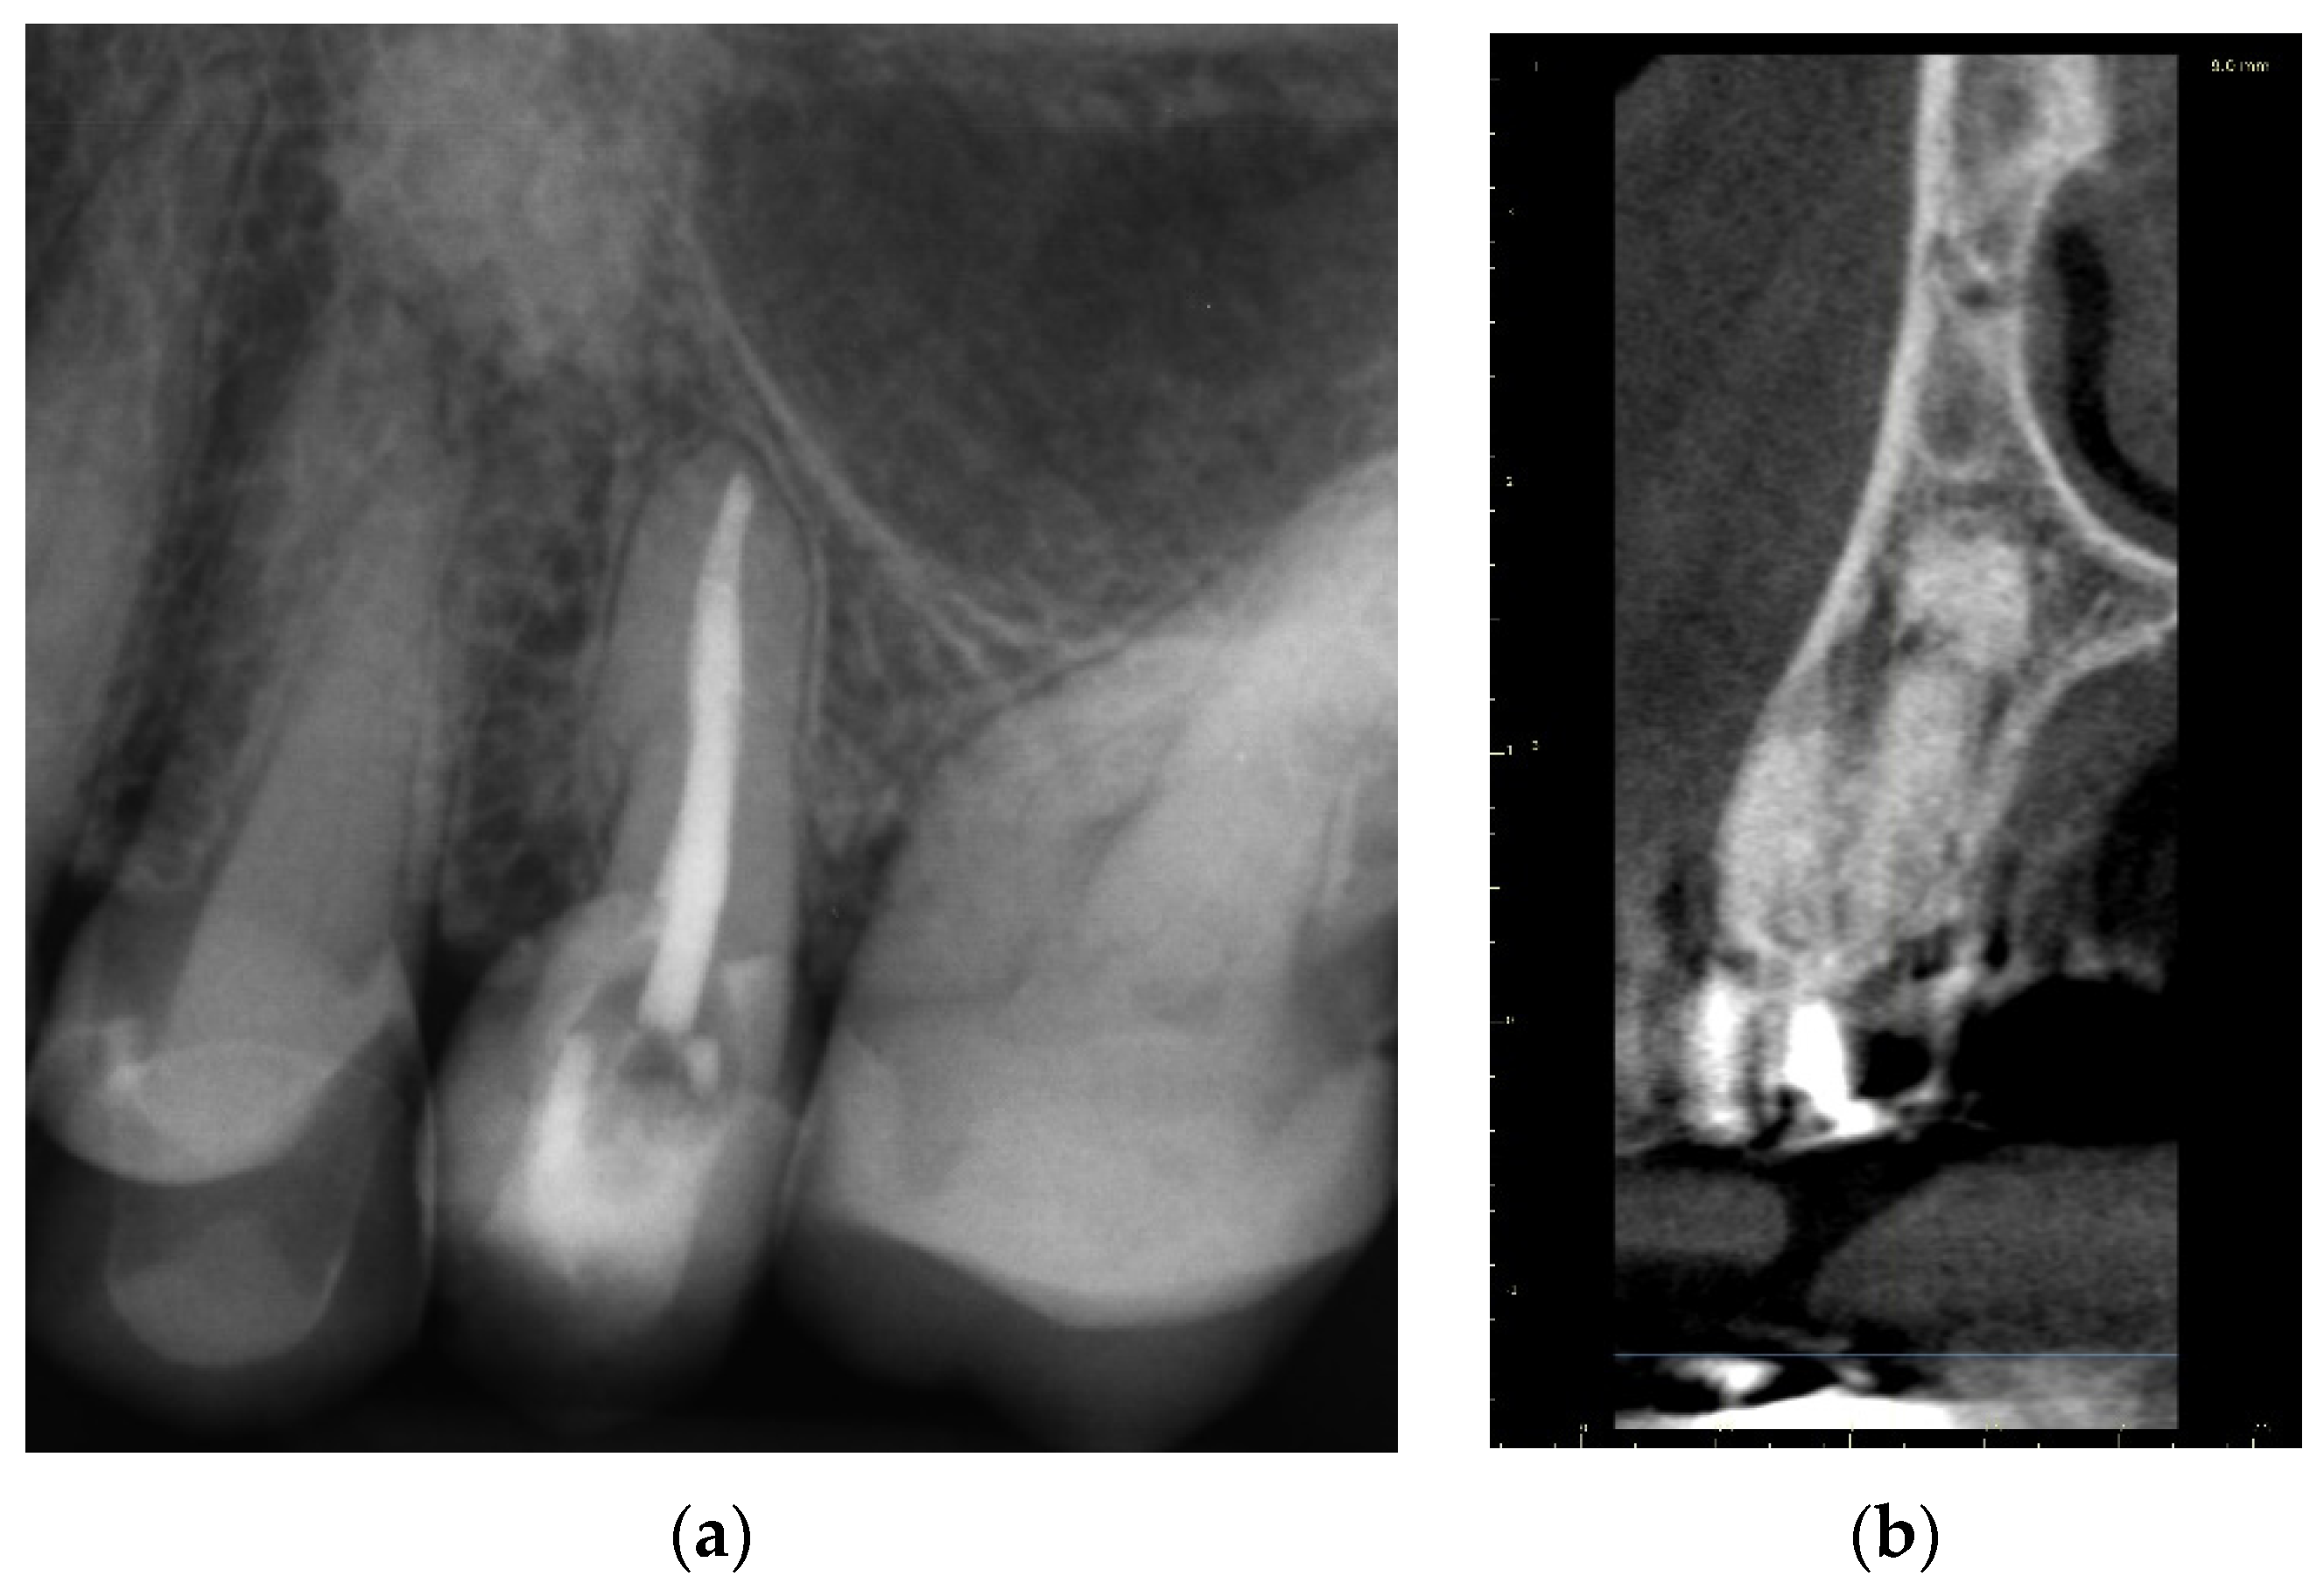

2.2.2. Case Report—Patient D: Symptomatic Pulp Necrosis with Pulp Canal Obliteration